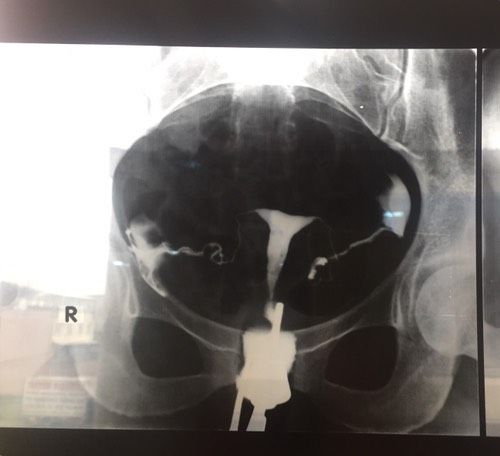

Рентген труб.Девочки добрый день, к гинекологу попаду только через несколько дней, помогите разобраться как вы считаете все ли в порядке?

Трубы проходимы но луче всё таки к врачу.

Ой лучше дождитесь гинеколога. Я вот первый раз такой снимок вижу и как по мне то проходимость хорошая)